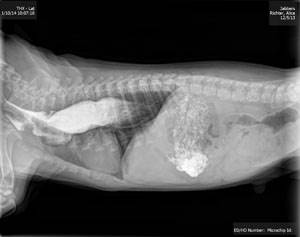

Мегаэзофагус – расширение всего пищевода вследствие его пареза или паралича.

В норме моторика пищевода обеспечивает движение пищи и воды от глотки к желудку. Заболевание гораздо чаще встречается у собак, чем у кошек. Различают врожденный и приобретенный мегаэзофагус. В первом случае заболевание регистрируется у щенков и молодых собак (примерно 1/3 случаев). Причем расширение пищевода может наблюдаться у всех щенков в помете. Таким образом, у определенных пород собак мегаэзофагус должен рассматриваться как генетическое заболевание (жесткошерстный фокстерьер, цвергшнауцер, немецкая овчарка, немецкий дог, ирландский сеттер).

Диагностика

Основывается на данных анамнеза, клинической картине. Крайне важно выяснить, является ли расширение пищевода самостоятельным заболеванием, или патология вторична по отношению к